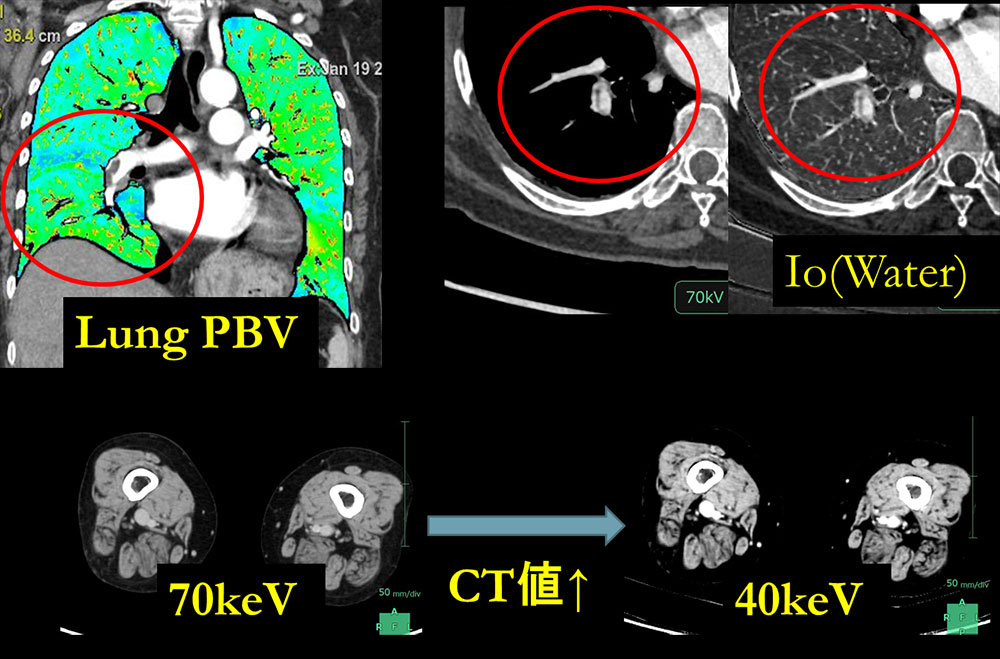

肺動脈塞栓症例では、血栓の有無の評価を行うだけでなく肺野内の造影剤分布、つまりヨードマップを可視化できることがメリットである。Fig3のように造影CT画像とヨードマップ画像をFusionすることで肺動脈の形態や肺血流の評価を同時に評価することができる。また、ヨード画像では血栓が視覚的に診断しやすいとのことで臨床画像として提出している。また、深部静脈血栓では低エネルギー画像を作成することでコントラストの上昇が得られ、診断において有用な画像となっている。

RevolutionCT_Minamitohoku04.jpg

Fig3, 肺塞栓におけるMD画像、

下肢深部静脈血栓での低keV画像の有用性

本来ダイナミックCTを行う目的であったが、患者の造影ラインの影響で造影剤の注入が予定より伸びてしまい、十分にCT値が得られなかったことがある。主治医の指示でこの症例(Fig6)はDECTで撮影しており低エネルギー画像を作成することで動脈相のようにVR画像を作成できた症例であった。50keVでは70keVと比べ約2倍、40keVでは70keVと比べ約3倍のCT値を得ることができ、不測の事態でフォローを行うことができた症例である。

RevolutionCT_Minamitohoku07.jpg

Fig6, 造影不良時の低keVにおけるCT値のリカバリー